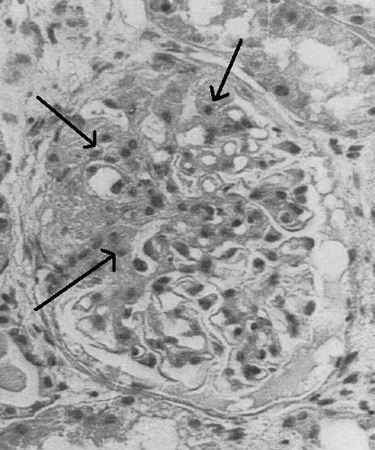

Microscopia óptica de biópsia renal demonstrando lesões típicas de glomeruloesclerose segmentar focal

Adaptado de Nagi AH, Alexander F, Lannigan R. Light and electron microscopical studies of focal glomerular sclerosis. J Clin Pathol. 1971 Dec;24(9):846-50